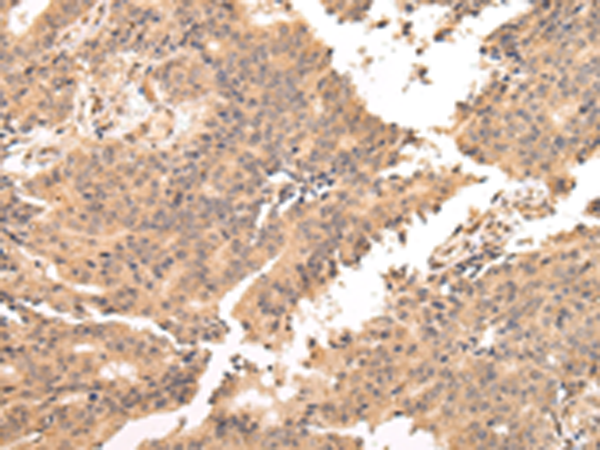

分类: 科研抗体货号: P08956别名: 65K; SAD1; CGI-21; HSPC332; SNRNP65应用: IHC反应种属: Human, Mouse